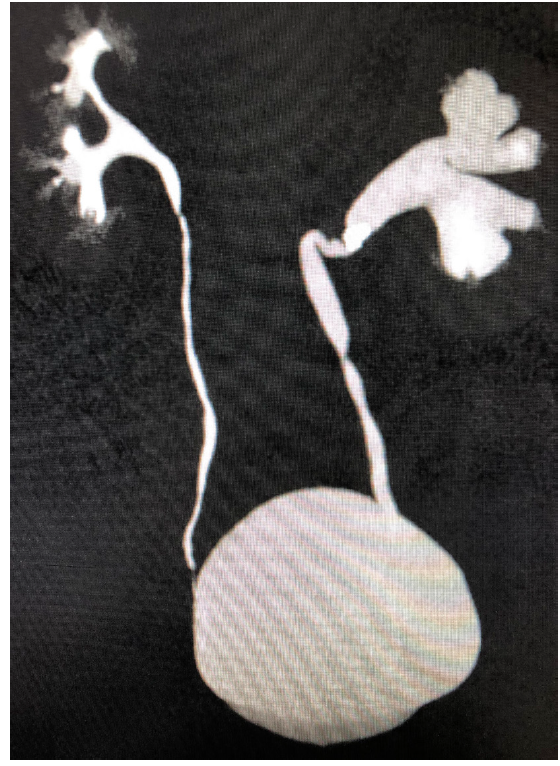

所有患者术前均进行了CTU(图1)。如果CTU显影不佳,做逆行造影可显示输尿管形态,必要时可做顺行造影+逆行造影,这样可显示患侧的整条尿路形态。或者行IVU、尿常规以及中段尿培养,排除手术禁忌证。尿培养阳性的患者术前给予敏感抗生素足量治疗,直至复查尿培养为阴性。既往有高血压和糖尿病史的患者,术前控制血压和血糖在手术安全范围内。所有的手术均由同一团队完成。

图1 一例典型输尿管上段嵌顿性结石合并输尿管迂曲患者的CTU图像